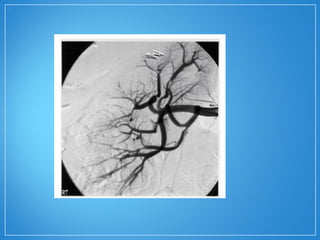

A angiografia seletiva da região abdominal

(tronco celíaco e artérias renais) pode evidenciar

a presença de estenoses irregulares e de

múltiplos microaneurismas característicos da

PAN.

• O diagnósticoda PAN depende da evidência histológica de vasculite. A biopsia de órgãos clinicamente afetados, como nervos periféricos, testículo e pele, tem uma sensibilidade de 65%. A angiografia seletiva da região abdominal (tronco celíaco e artérias renais) pode evidenciar a presença de estenoses irregulares e de múltiplos microaneurismas característicos da PAN.